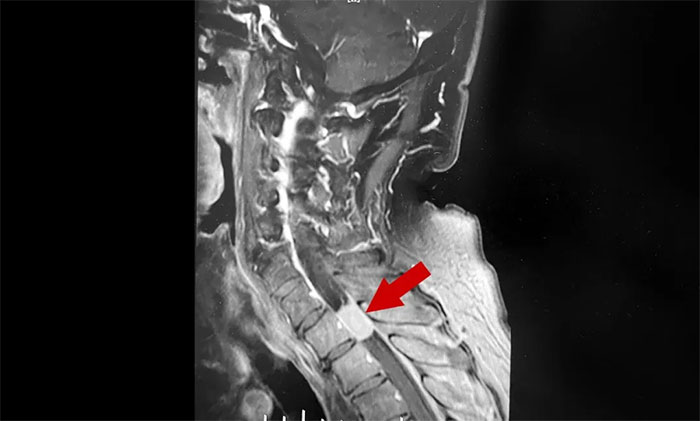

半個(gè)月前,陳阿姨發(fā)現(xiàn)左手臂麻木感越來越強(qiáng)烈,做家務(wù)都有點(diǎn)無力,還出現(xiàn)了胸部麻木和膝蓋疼痛,這才在家人的陪同下到當(dāng)?shù)蒯t(yī)院求診。經(jīng)頸椎核磁共振檢查,結(jié)果顯示頸髓椎管內(nèi)腫瘤。困擾陳阿姨多年的上肢麻木不是頸椎病,而是腫瘤所致。

▲ 雙手麻木要警惕頸髓椎管內(nèi)腫瘤